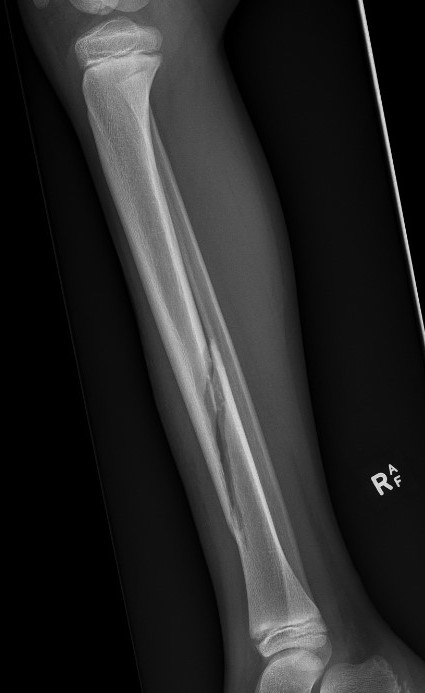

Displaced Tibial Shaft Fractures

Acceptable reduction

- varus / valgus < 5o

- anterior / posterior < 5o

- rotation 5o

- shortening 10 mm